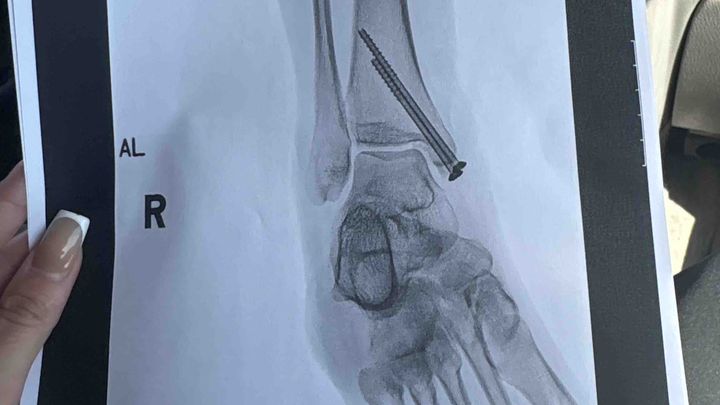

My car was immediately deemed totaled. I had just bought the car with cash only 3 months ago, but that isn’t what I am creating this for. The emts cut my pants because I had a deep to the bone laceration. I had then got into the ambulance and to Halifax I went. I could barely move my right leg especially ankle, was veryyy bruised / swollen. After some x rays what I had hoped was not the case in fact was. Three fractures in my right ankle as well as a fractured patella inside the laceration.. resulting in surgery + 2 screws in my ankle for life + 8 stitches on ankle, 12 stitches on knee and 2 inside knee.